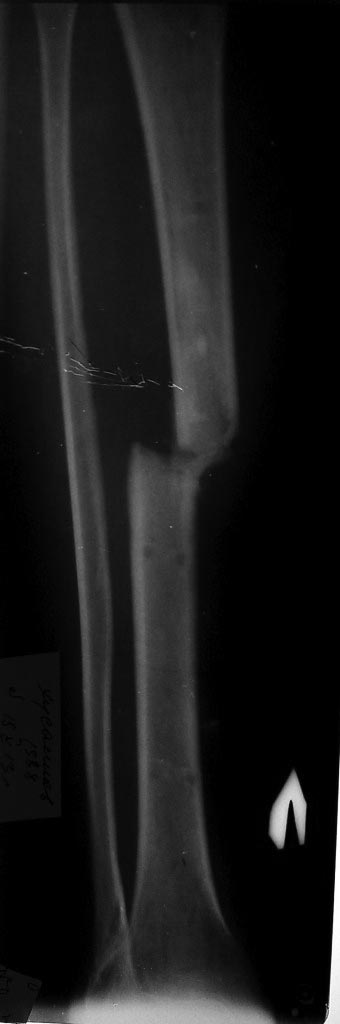

Ничего подобного не замечал особенно на голени.С аппаратом Илизарова мы пережили тяжелое время- девяностые когда кроме спиц ничего не было,заместили кучу дефектов на фоне остеомиелита и все срасталось и не было контрактур особенно в коленном суставе.Нужно просто не нарушать методику проведения спиц.Этот перелом требует не трансплантации ,а адекватной репозиции и жесткой фиксации и не повредила бы ранняя нагрузка на конечность.Посмотрите на снимок-дистальный отломок как будто протянул маленькую ручку к проксимальному-вроде как просит- приблизь его и мы сольемся воедино!

С вами согласен полностью, сколько мы прооперировали пациентов в 90-х!!!!! Всё срасталось на ура! Тут нужен внеочаговый остеосинтез , каким аппаратом? - это выбор мастера - репозиция + остеотомия м/берцовой кости!

Согласен с Андереем Кияночкиным. Вопрос давно решенный: с биологией голени все в порядке, потенциал к сращению не утерян . После этапной постепенной коррекции деформации любой метод СТАБИЛИЗАЦИИ перелома приемлем и функционален: БИОС,АВФ,LCP,DCP.